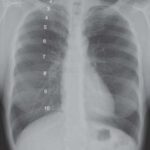

Si la tasa neta de movimiento de líquido excede la capacidad de drenaje del sistema linfático, el líquido comienza a acumularse en los tejidos, dando lugar al edema. Este edema puede ser localizado o generalizado, dependiendo de la causa subyacente y la gravedad del trastorno. Además, si la acumulación de líquido ocurre en una superficie serosa, como la cavidad pleural, pericárdica o peritoneal, se denomina derrame.

Los trastornos cardiovasculares, renales o hepáticos pueden desencadenar este desequilibrio en los mecanismos reguladores del fluido corporal. Por ejemplo, la insuficiencia cardíaca congestiva puede aumentar la presión hidrostática vascular, lo que lleva a la acumulación de líquido en los tejidos. La insuficiencia renal puede provocar una retención de sodio y agua, aumentando así la presión hidrostática vascular. Mientras tanto, las enfermedades hepáticas pueden disminuir la síntesis de proteínas plasmáticas, reduciendo la presión coloidosmótica y favoreciendo la salida de líquido de los vasos sanguíneos hacia los tejidos.

Por otro lado, los edemas y derrames no inflamatorios son causados por procesos que no involucran inflamación activa en los tejidos o vasos sanguíneos. Estos líquidos acumulados, conocidos como trasudados, son pobres en proteínas y generalmente contienen células escasas o ausentes. Los edemas y derrames no inflamatorios son comunes en una variedad de trastornos, como la insuficiencia cardíaca, la insuficiencia hepática, las nefropatías y la malnutrición.

En la insuficiencia cardíaca, por ejemplo, la disminución de la función del corazón conduce a una acumulación de líquido en los tejidos debido a una disminución en la presión coloidosmótica y un aumento en la presión hidrostática venosa. En la insuficiencia hepática, la disminución en la síntesis de proteínas hepáticas, incluida la albúmina, contribuye a una disminución en la presión coloidosmótica, lo que favorece la formación de trasudados.